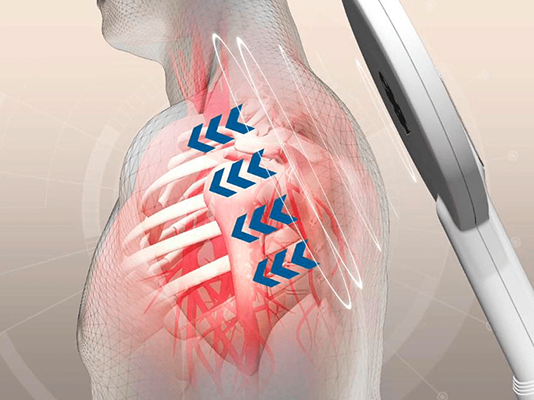

Neuromodulación y electrólisis percutánea intratisular (EPI®)

La máquina más potente del mercado. Estimulación de estructuras profundas. Efectos en dolor agudo y crónico, fracturas y edemas óseos, estimulación del sistema nervioso, incontinencias, trastornos musculoesqueléticos…